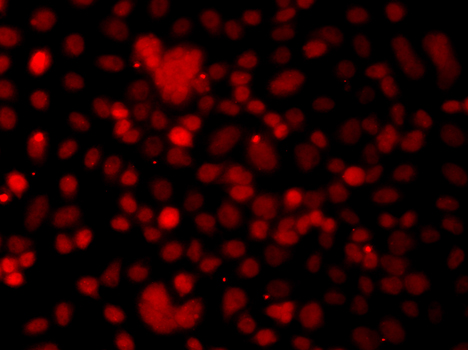

Immunofluorescence analysis of MCF7 cell using SNAI2 antibody. Blue: DAPI for nuclear staining.

Immunofluorescence analysis of U2OS cell using SNAI2 antibody. Blue: DAPI for nuclear staining.

Immunofluorescence analysis of A549 cell using SNAI2 antibody. Blue: DAPI for nuclear staining.

Immunofluorescence analysis of A549 cell using SNAI2 antibody.